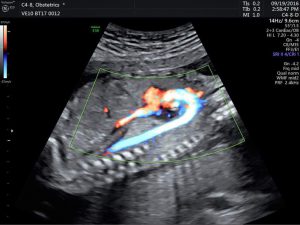

Siêu âm 2D, 3D, 4D là những phương pháp phổ biến nhất để kiểm tra ...

Siêu âm thai rất quan trọng trong suốt thai kỳ, giúp bác sĩ kiểm tra ...